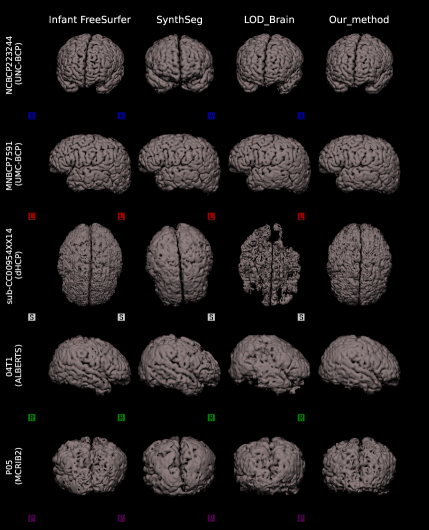

5.2 Qualitative comparisons on raw infant data

To provide a clear visual assessment of segmentation performance, we present a diverse set of qualitative results obtained using different methods. Figs 4 and 5 illustrate a side-by-side comparison between the competing approaches and the silver-standard ground truth generated by Infant FreeSurfer. Specifically, we highlight the 30 most discordant MRI volumes, identified as those exhibiting the highest variance in DICE scores across the evaluated methods when compared to Infant FreeSurfer segmentations. By focusing on these challenging cases, we enhance the visibility of key differences in anatomical structure delineation, allowing for a more insightful comparison of method effectiveness.

This visualization strategy ensures that performance disparities between compared approaches are clearly distinguishable, providing an intuitive and informative perspective on the strengths and limitations of each method, including our proposed solution.

5.2.1 Surface analysis on raw infant data

We perform a surface-based analysis using all methods, that are Infant FreeSurfer, SynthSeg, LOD-Brain, and LODi, to evaluate segmentation performance across different anatomical surfaces. Specifically, we analyze the surfaces of the inner gray matter (Fig.7(a)), and of the outer gray matter (Fig.7(b)).

This analysis is conducted on five MRI volumes, each selected from a different dataset (BCP-UMN-site, BCP-UNC-site, dHCP, ALBERTS, and MCRIB2), based on the scan exhibiting the highest variance in Dice scores across methods. Similar to the qualitative comparison, this selection strategy emphasizes cases where segmentation results show the greatest discrepancies.

By visualizing these 3D surface representations, generated using nii2mesh, we provide a more detailed assessment of LODi?s ability to accurately capture anatomical brain structures. Notably, this approach also highlights the smoothness of the resulting segmentations, and facilitates a direct comparison with benchmark methods, offering deeper insights into segmentation performance across different surfaces.